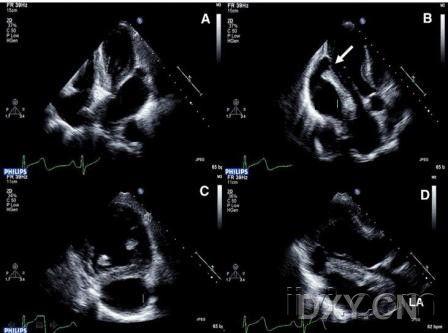

感染性心内膜炎伴急性心梗一例

前壁心肌梗死病例介绍,心电图特征,冠脉造影以及经食道超声心动图(tee

心肌梗塞的超声表现

原创华医心诚医生集团专家杨颖:冠心病超声诊断之心梗并发症